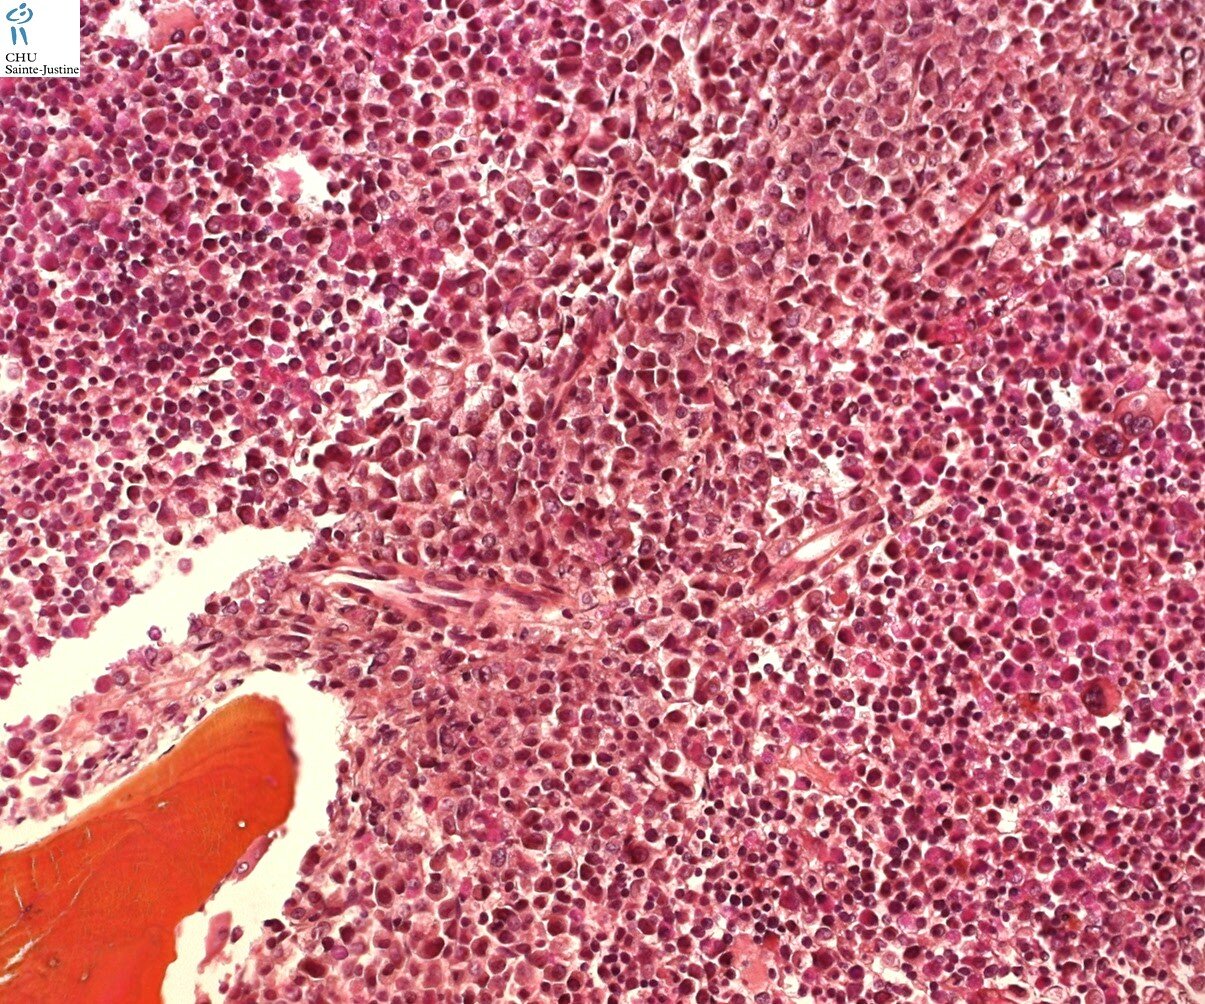

Morphology